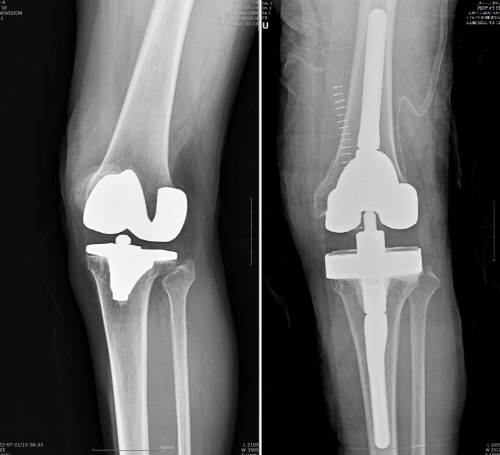

인공관절 재치환은 빙판길 낙상사고 등 외상으로 문제가 생기거나, 인공관절을 오래 써서 닳아 흔들리거나 염증‧감염으로 인해 인공관절이 제 기능을 하지 못하고 통증을 일으키면 한다.

정형외과 전문의들이 너무 젊은 나이에 인공관절 수술하기보다 가급적 65~70세 사이에 한 번만 수술을 받을 것을 권장한다. 특히 인공관절 재치환은 많은 경우 골 소실과 연부조직 손상을 동반하는 만큼 수술 자체도 까다롭고, 처음 수술보다 결과가 좋지 않을 수도 있다.